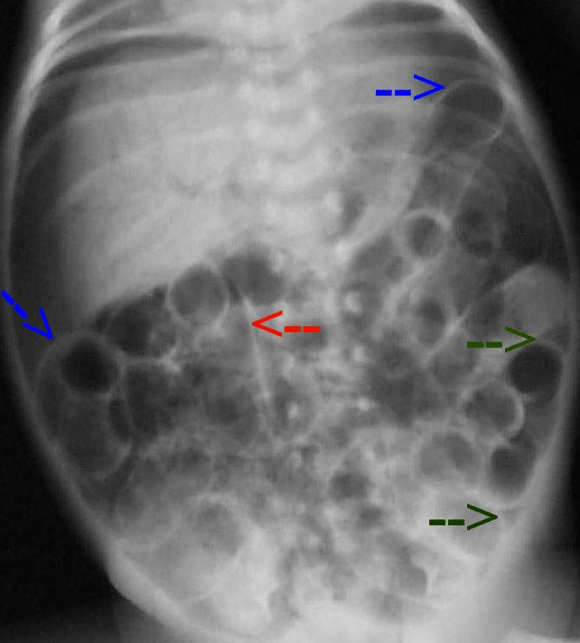

From atlas.mudr.org

Radiology case Necrosis of descending colon, colostomy Colostomy Necrosis Common early complications include leakage and skin irritations, high output resulting in fluid and electrolyte imbalances, or stoma necrosis; These complications can lead to a loss of function at the stoma site or even tissue death (necrosis). The creation of an ileostomy or colostomy is a common surgical event, both in elective and in emergency context. The seven most common. Colostomy Necrosis.